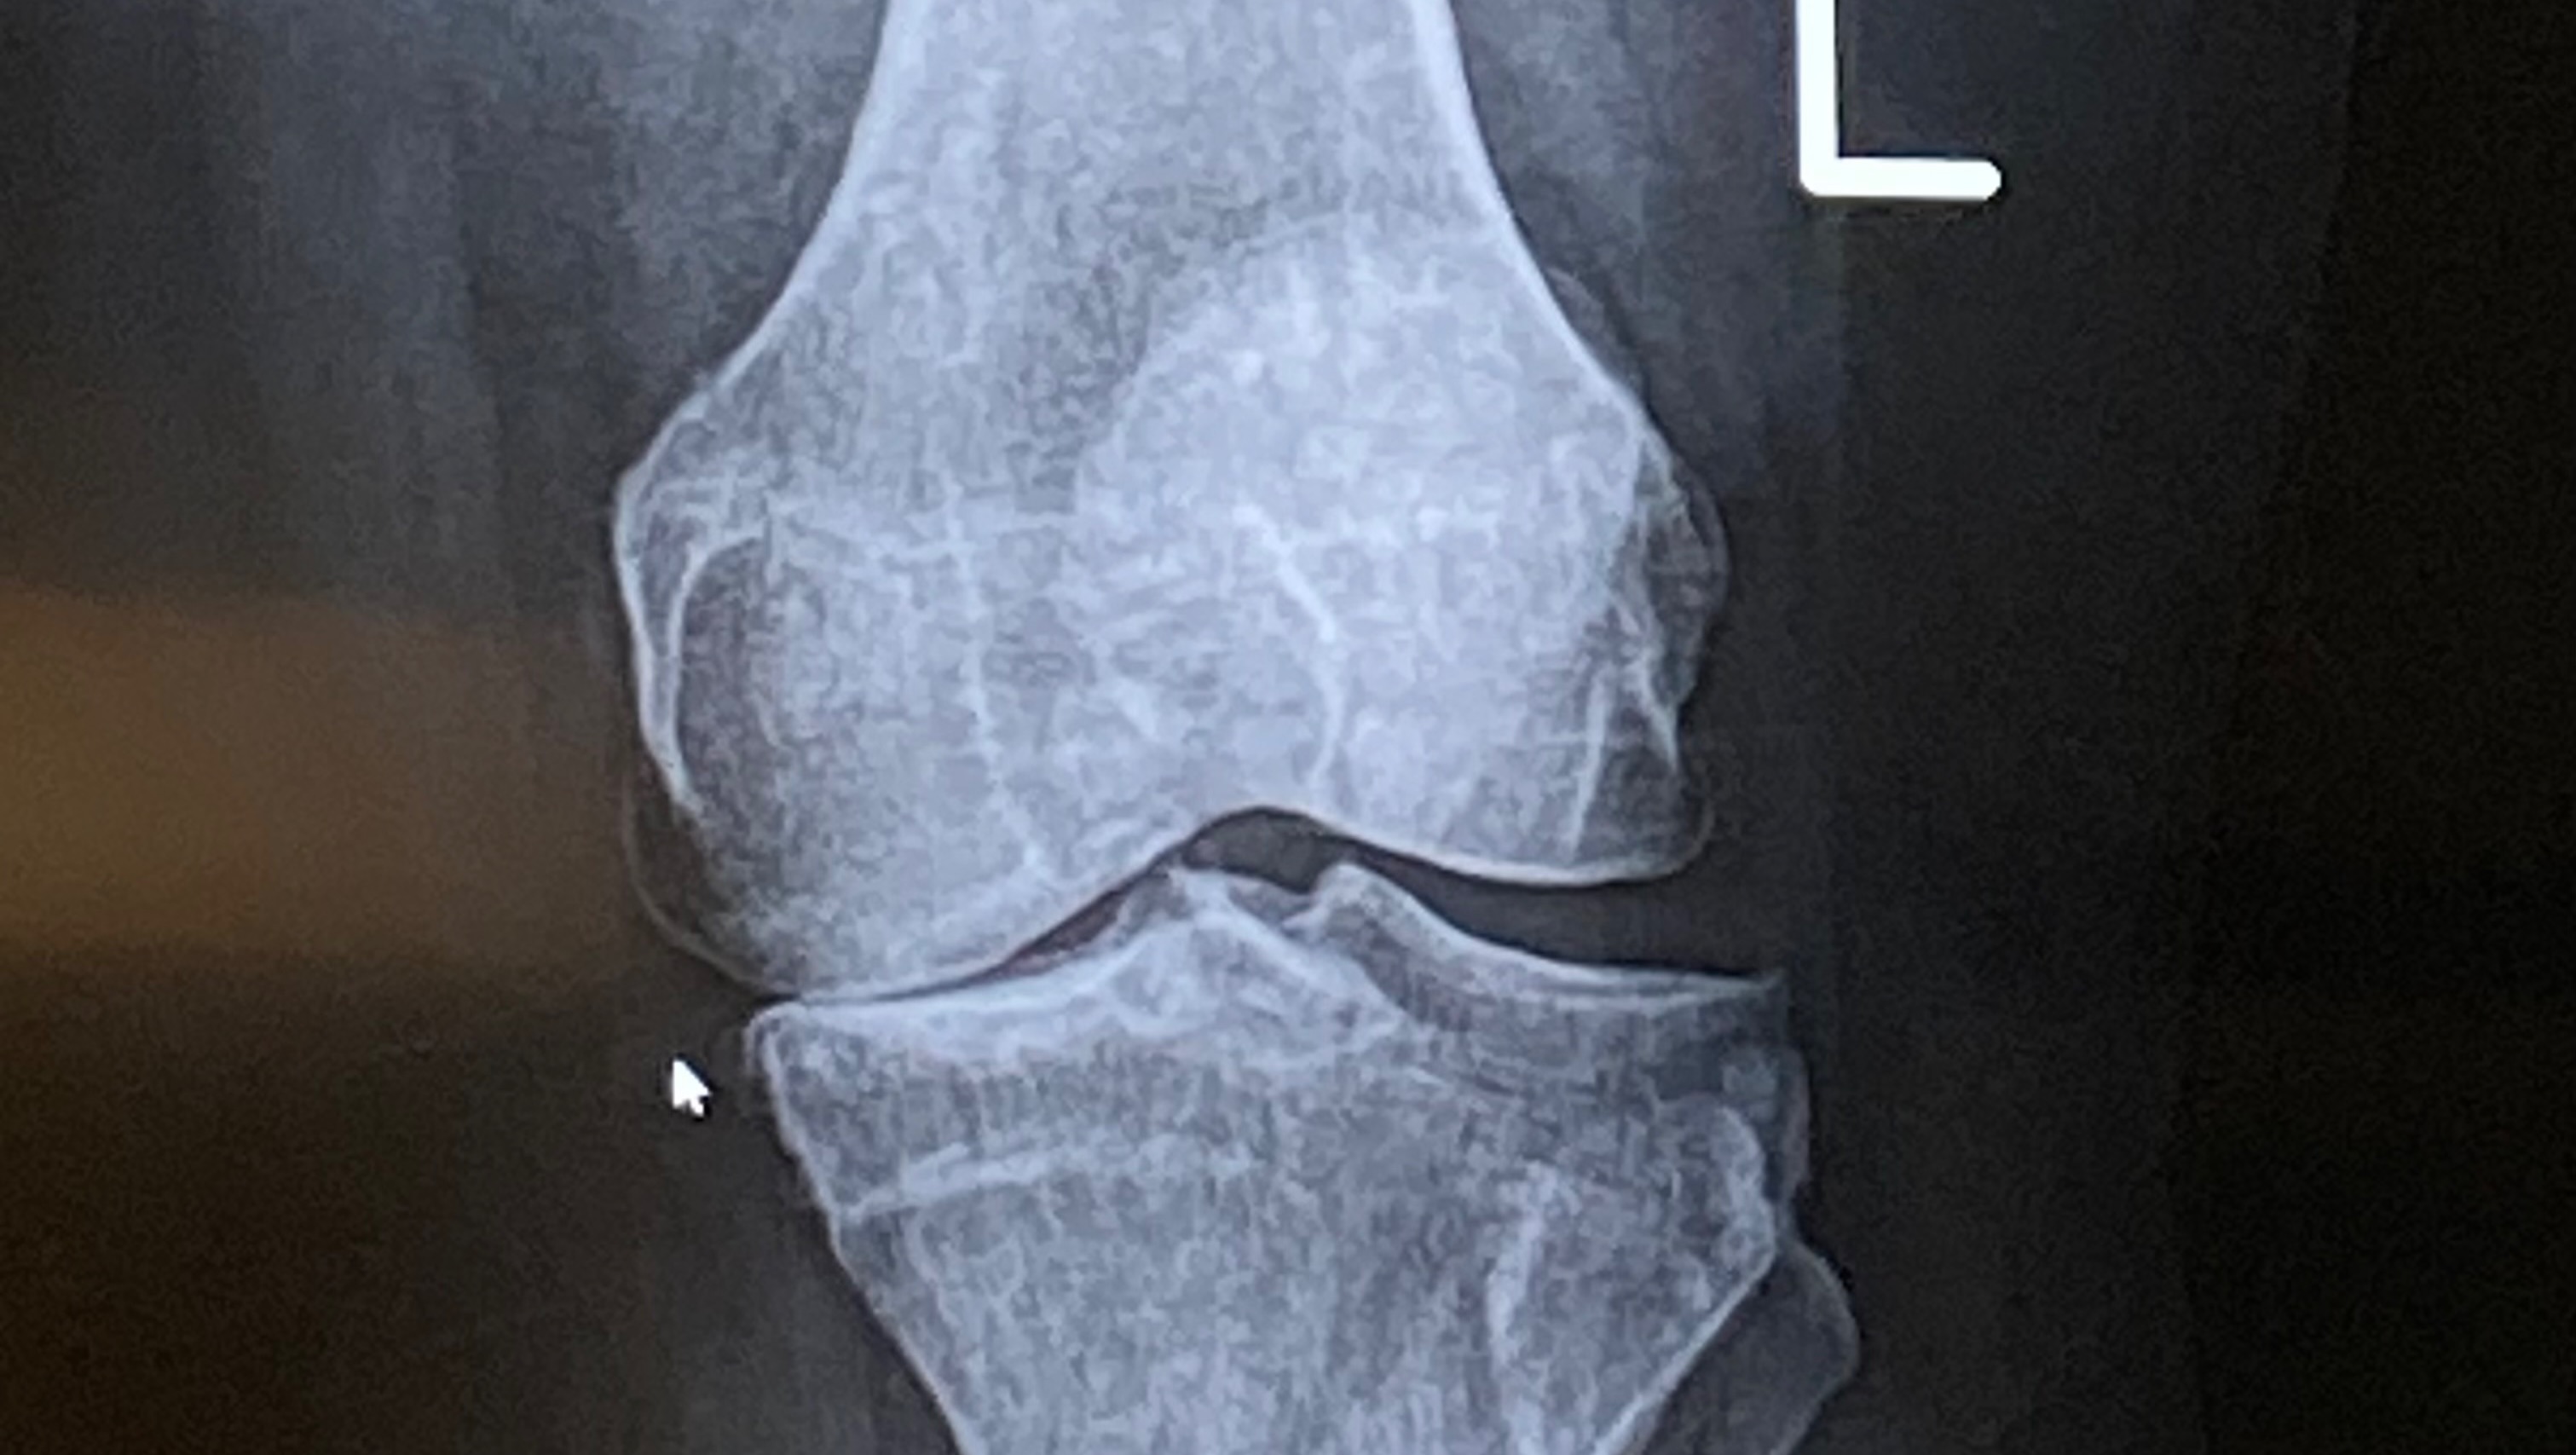

The pain in my knees is constant. I’m bone-on-bone in my left inner knee and right outer knee. It’s getting worse every single day. Walking is becoming nearly impossible, and without help, I’ll end up in a wheelchair permanently.

When I talked to my doctor about knee replacements, I was told it’s too risky for me. If I were to get an infection after surgery, I could lose my legs. The only option left for me is stem cell therapy – a much safer, non-surgical approach. But the problem is: insurance doesn’t cover it. Not mine, not anyone’s. It costs about $7,000-$8,000 per knee, and I need both done.